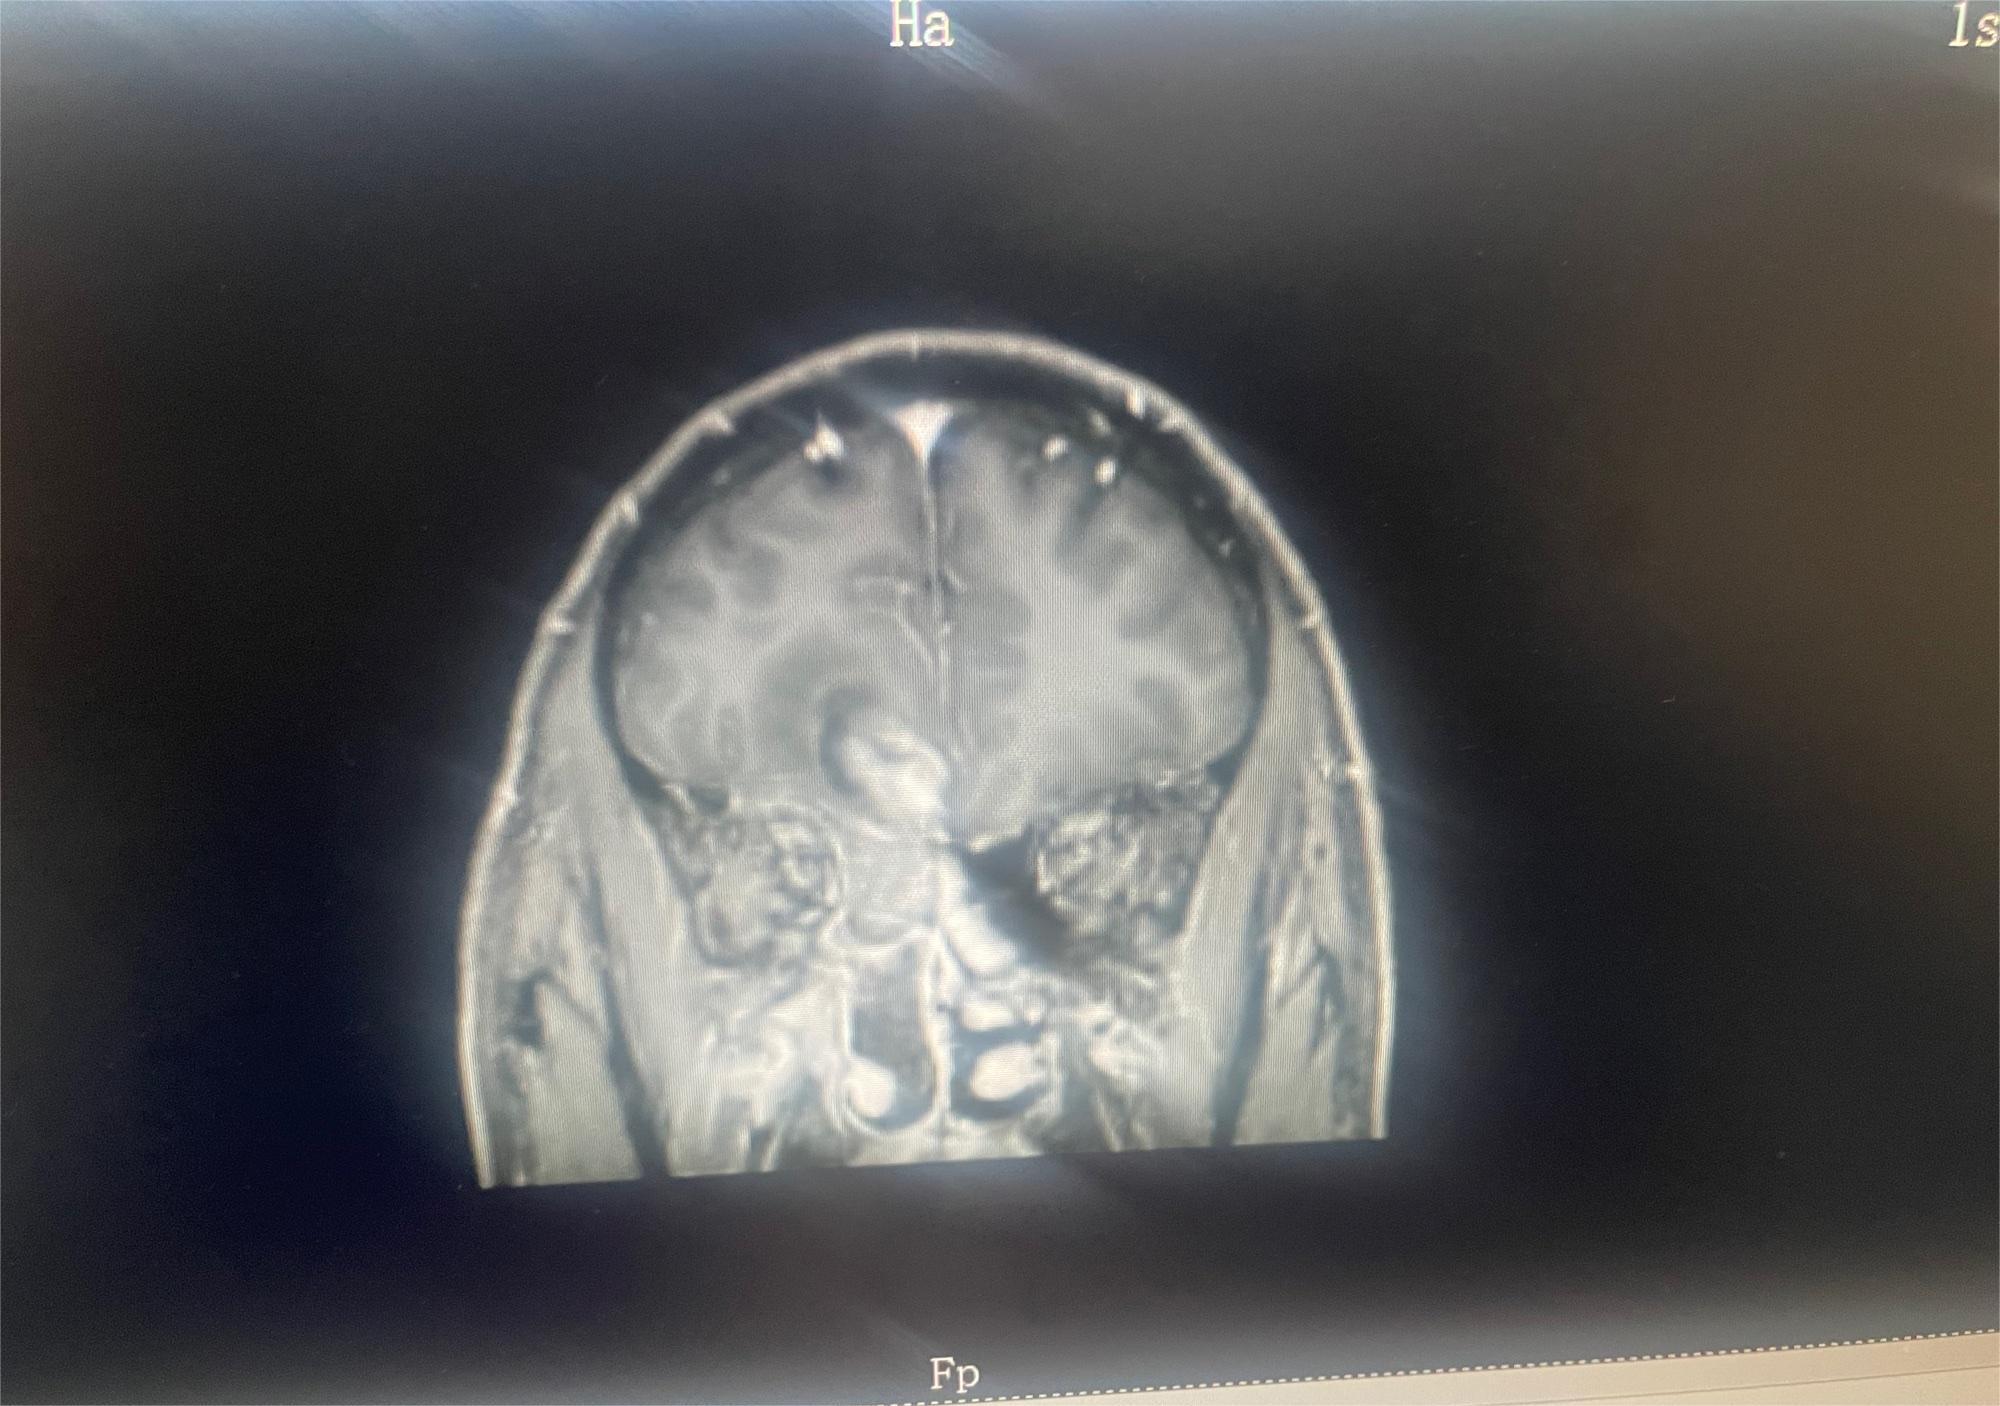

这是我83岁奶奶的报告,哪位朋友能帮忙看看这是到什么阶段了,发展到晚期还有多长时间。 医生说肿瘤挨着血管,做不了手术,年...

共1张

这是早期还是晚期的肿瘤呢